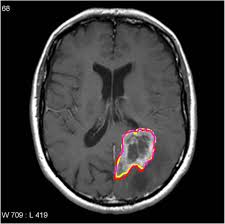

Brain Tumor Detection Using MRI Segmentation

Advancing Brain Tumor Diagnosis with AI-Powered Image Segmentation. A cutting-edge AI solution utilizing deep learning architecture to enhance brain tumor segmentation and classification, aiding clinicians in accurate diagnosis and treatment planning

• Medical imaging plays a pivotal role in diagnosing and planning treatment for brain tumors, which affect millions globally. Accurate segmentation and classification of brain tumors from medical images are crucial to assist clinicians in understanding tumor characteristics.

• A client required an AI-powered solution to improve brain tumor diagnosis. The main challenge was the time-consuming and complex manual process of delineating tumor boundaries and classifying different tumor types. The objective is to explore 2D Image Segmentation using neural networks for brain tumor classification and segmentation.

• Automated segmentation and classification methods can significantly reduce the time required for manual analysis, improving clinical workflows and decision-making for medical professionals.

• Leveraged a custom dataset combining three widely used datasets for evaluating medical image analysis methods. The dataset covers gliomas, meningiomas, and pituitary tumors and includes multi-modal MRI images with expert pixel-level annotations for tumor regions.

• The neural network, with a multi-layered structure, was selected for segmentation. Hidden layers capture hierarchical features, and the output layer reconstructs a pixel-wise segmentation map. Non-linear activations and backpropagation optimize learning for accurate tumor boundary localization.

• Implemented an AI-driven system that:

• Accurately segments and classifies brain tumors from MRI images.

• Assists clinicians in tumor delineation, quantification, and subtype identification.

• Enhances diagnosis, treatment planning, and monitoring of brain tumors.

Images :

• The AI-powered brain tumor segmentation solution significantly improves diagnostic accuracy, reducing manual effort and analysis time.

• Clinicians benefit from enhanced workflow efficiency, faster tumor identification, and improved treatment planning.

• Leads to better patient outcomes, increased operational efficiency in medical imaging, and scalable AI adoption in healthcare.